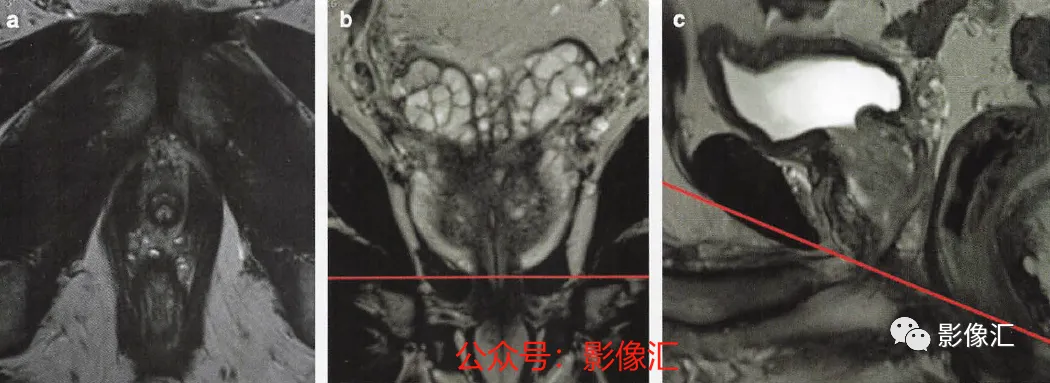

8. 前列腺尖部的横轴面(图2.26)